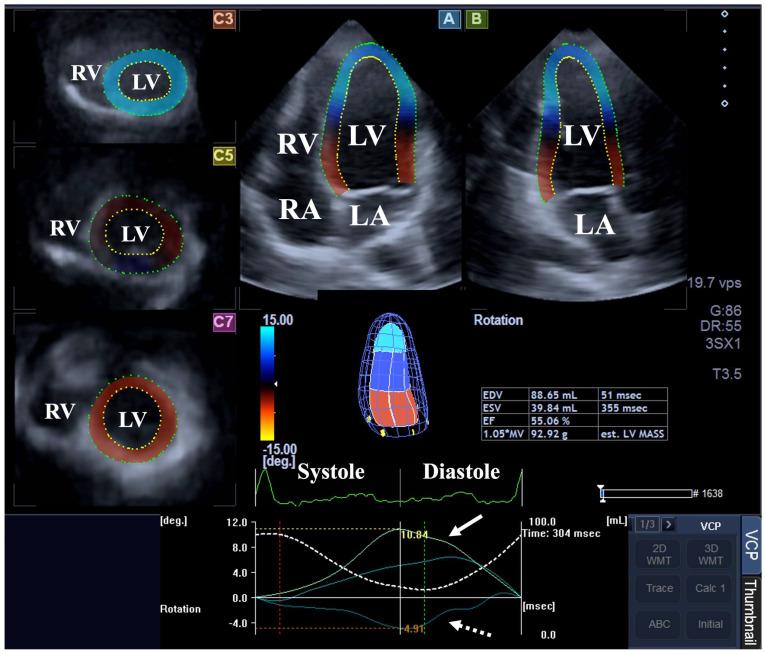

There is a balanced relationship between the left ventricle (LV), the aortic valve and the aorta, the functioning of which is essential for optimal circulation. Associations between simultaneously assessed LV rotational mechanics and aortic valve annular (AVA) dimensions respecting the cardiac cycle have never been assessed in clinical circumstances in healthy individuals by three-dimensional speckle-tracking echocardiography (3DSTE). The present study aimed to perform an extensive investigation in order to clarify their possible associations. The present study comprised 111 healthy individuals (mean age 35.3 ± 12.0 years, 69 males). With increase in end-diastolic AVA area, tendentious increase in apical LV rotation and consequential LV twist could be detected. Basal and apical rotations and LV twist were tendentiously higher in case of mean end-systolic AVA area compared to lower/higher than mean end-systolic AVA area. With increase in basal LV rotation, tendentious decrease in end-diastolic AVA dimensions could be detected. End-systolic AVA dimensions were tendentiously smaller in case of mean basal LV rotation compared to lower/higher than mean basal LV rotations. With increase in apical LV rotation, tendentious increase in end-diastolic AVA dimensions could be detected. End-systolic AVA dimensions were tendentiously higher in case of mean apical LV rotation compared to lower/higher than mean apical LV rotations. No obvious significant association could be detected between simultaneously assessed LV rotational mechanics and AVA dimensions respecting the cardiac cycle in healthy adults.